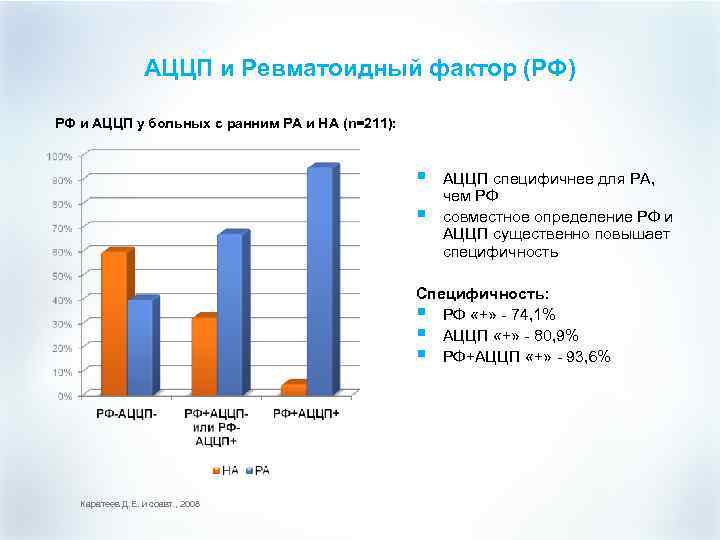

АЦЦП и Ревматоидный фактор (РФ) РФ и АЦЦП у больных с ранним РА и НА (n=211): § § АЦЦП специфичнее для РА, чем РФ совместное определение РФ и АЦЦП существенно повышает специфичность Специфичность: § РФ «+» - 74, 1% § АЦЦП «+» - 80, 9% § РФ+АЦЦП «+» - 93, 6% Каратеев Д. Е. и соавт. , 2008

АЦЦП и Ревматоидный фактор (РФ) РФ и АЦЦП у больных с ранним РА и НА (n=211): § § АЦЦП специфичнее для РА, чем РФ совместное определение РФ и АЦЦП существенно повышает специфичность Специфичность: § РФ «+» - 74, 1% § АЦЦП «+» - 80, 9% § РФ+АЦЦП «+» - 93, 6% Каратеев Д. Е. и соавт. , 2008